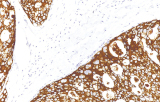

A imunohistoquímica (IHQ) com anticorpos primários CE/IVD é essencial para o diagnóstico e classificação precisos de malignidades ginecológicas e mamárias. Estes anticorpos permitem a deteção precisa de marcadores tumorais e proteínas celulares, apoiando o diagnóstico diferencial e guiando estratégias terapêuticas personalizadas.

Estudos recentes destacam o valor diagnóstico das proteínas do complexo SWI/SNF, particularmente ARID1B, na identificação de malignidades ginecológicas desdiferenciadas e indiferenciadas – tumores agressivos com mau prognóstico. A IHQ de ARID1B oferece elevada especificidade e está cada vez mais integrada em painéis diagnósticos para melhorar a precisão. Painéis com marcadores adicionais também apoiam a diferenciação de sarcomas uterinos, aumentando a exatidão diagnóstica. Evidência emergente sugere que ARID1B pode representar um alvo terapêutico potencial no carcinoma ovárico de células claras, embora as aplicações clínicas permaneçam em fase investigacional.